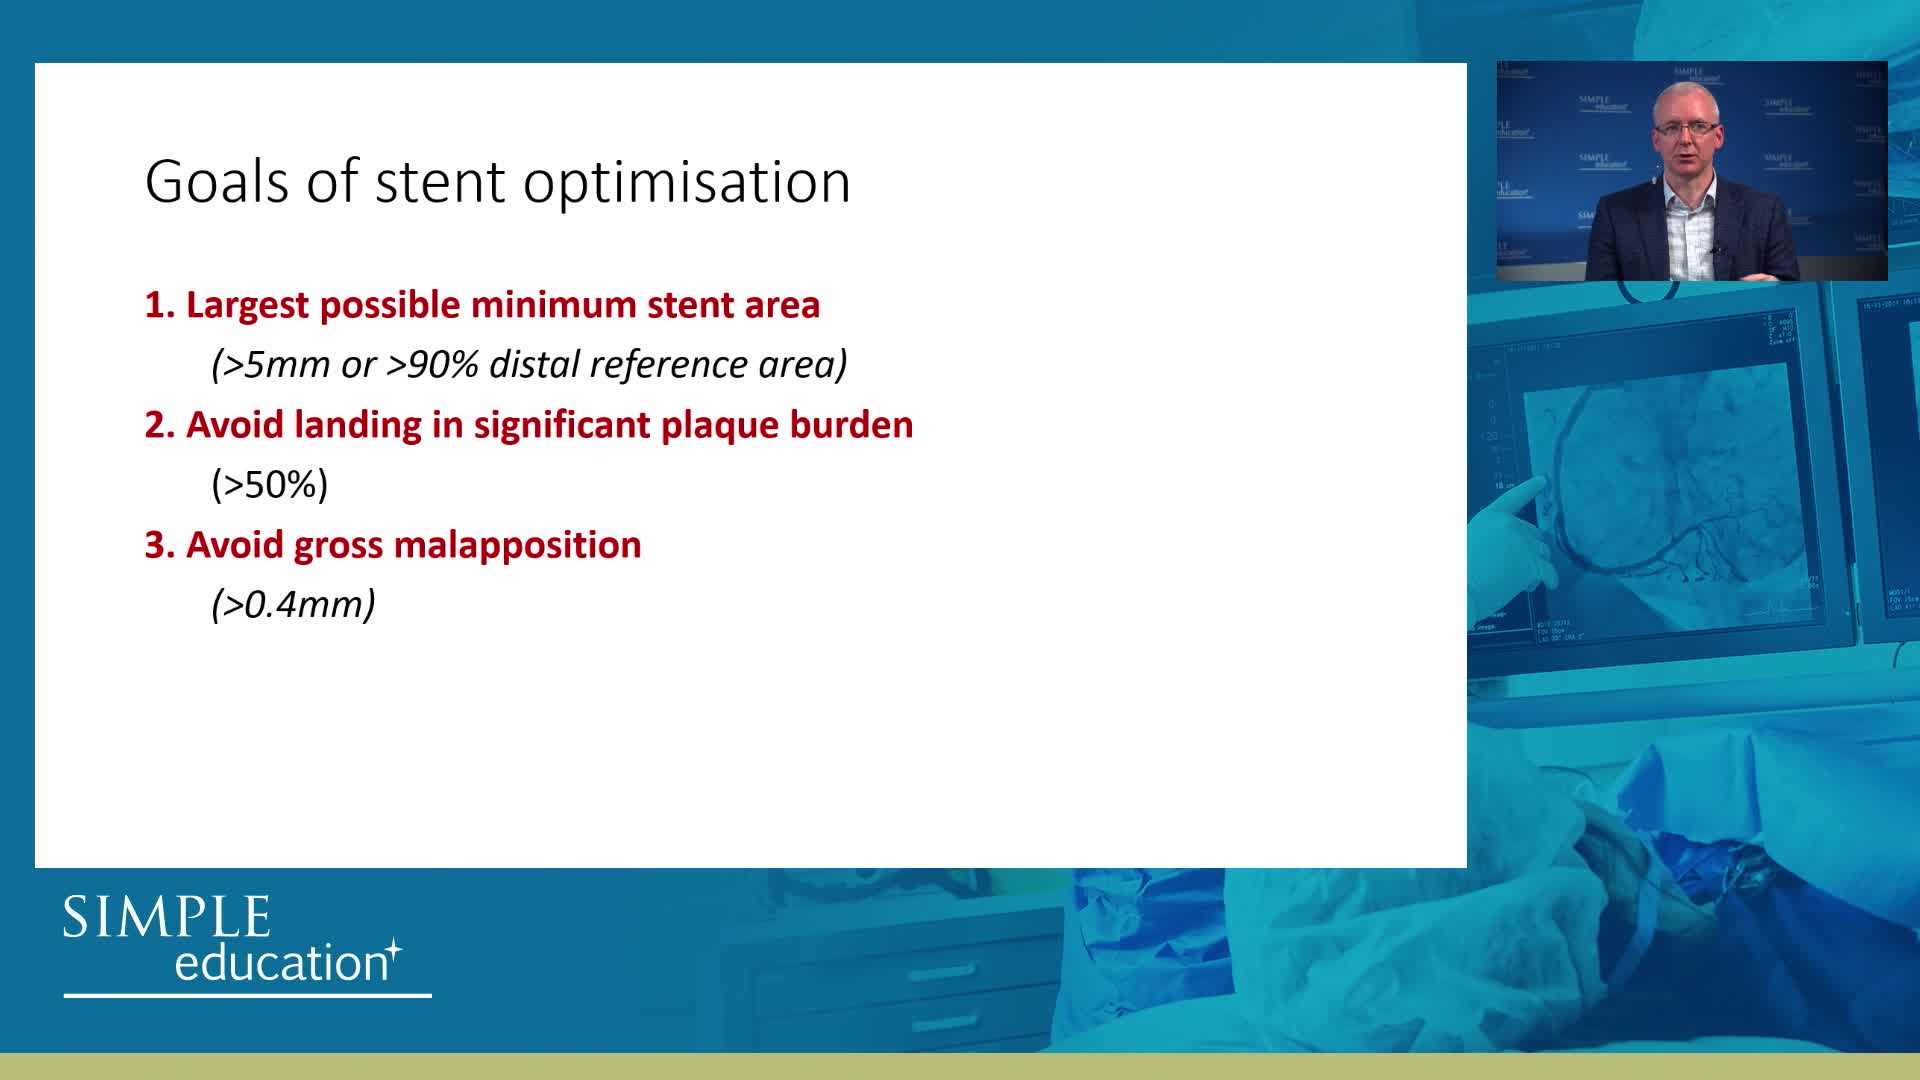

Best practices and personalised medicine in complex PCI - Prof Javier Escaned

Essential steps for physiology-based PCI planning and guidance - Dr Allen Jeremias

Using SyncVision Co-registration to distinguish between focal and diffuse coronary disease. - Prof Giuseppe Tarantini